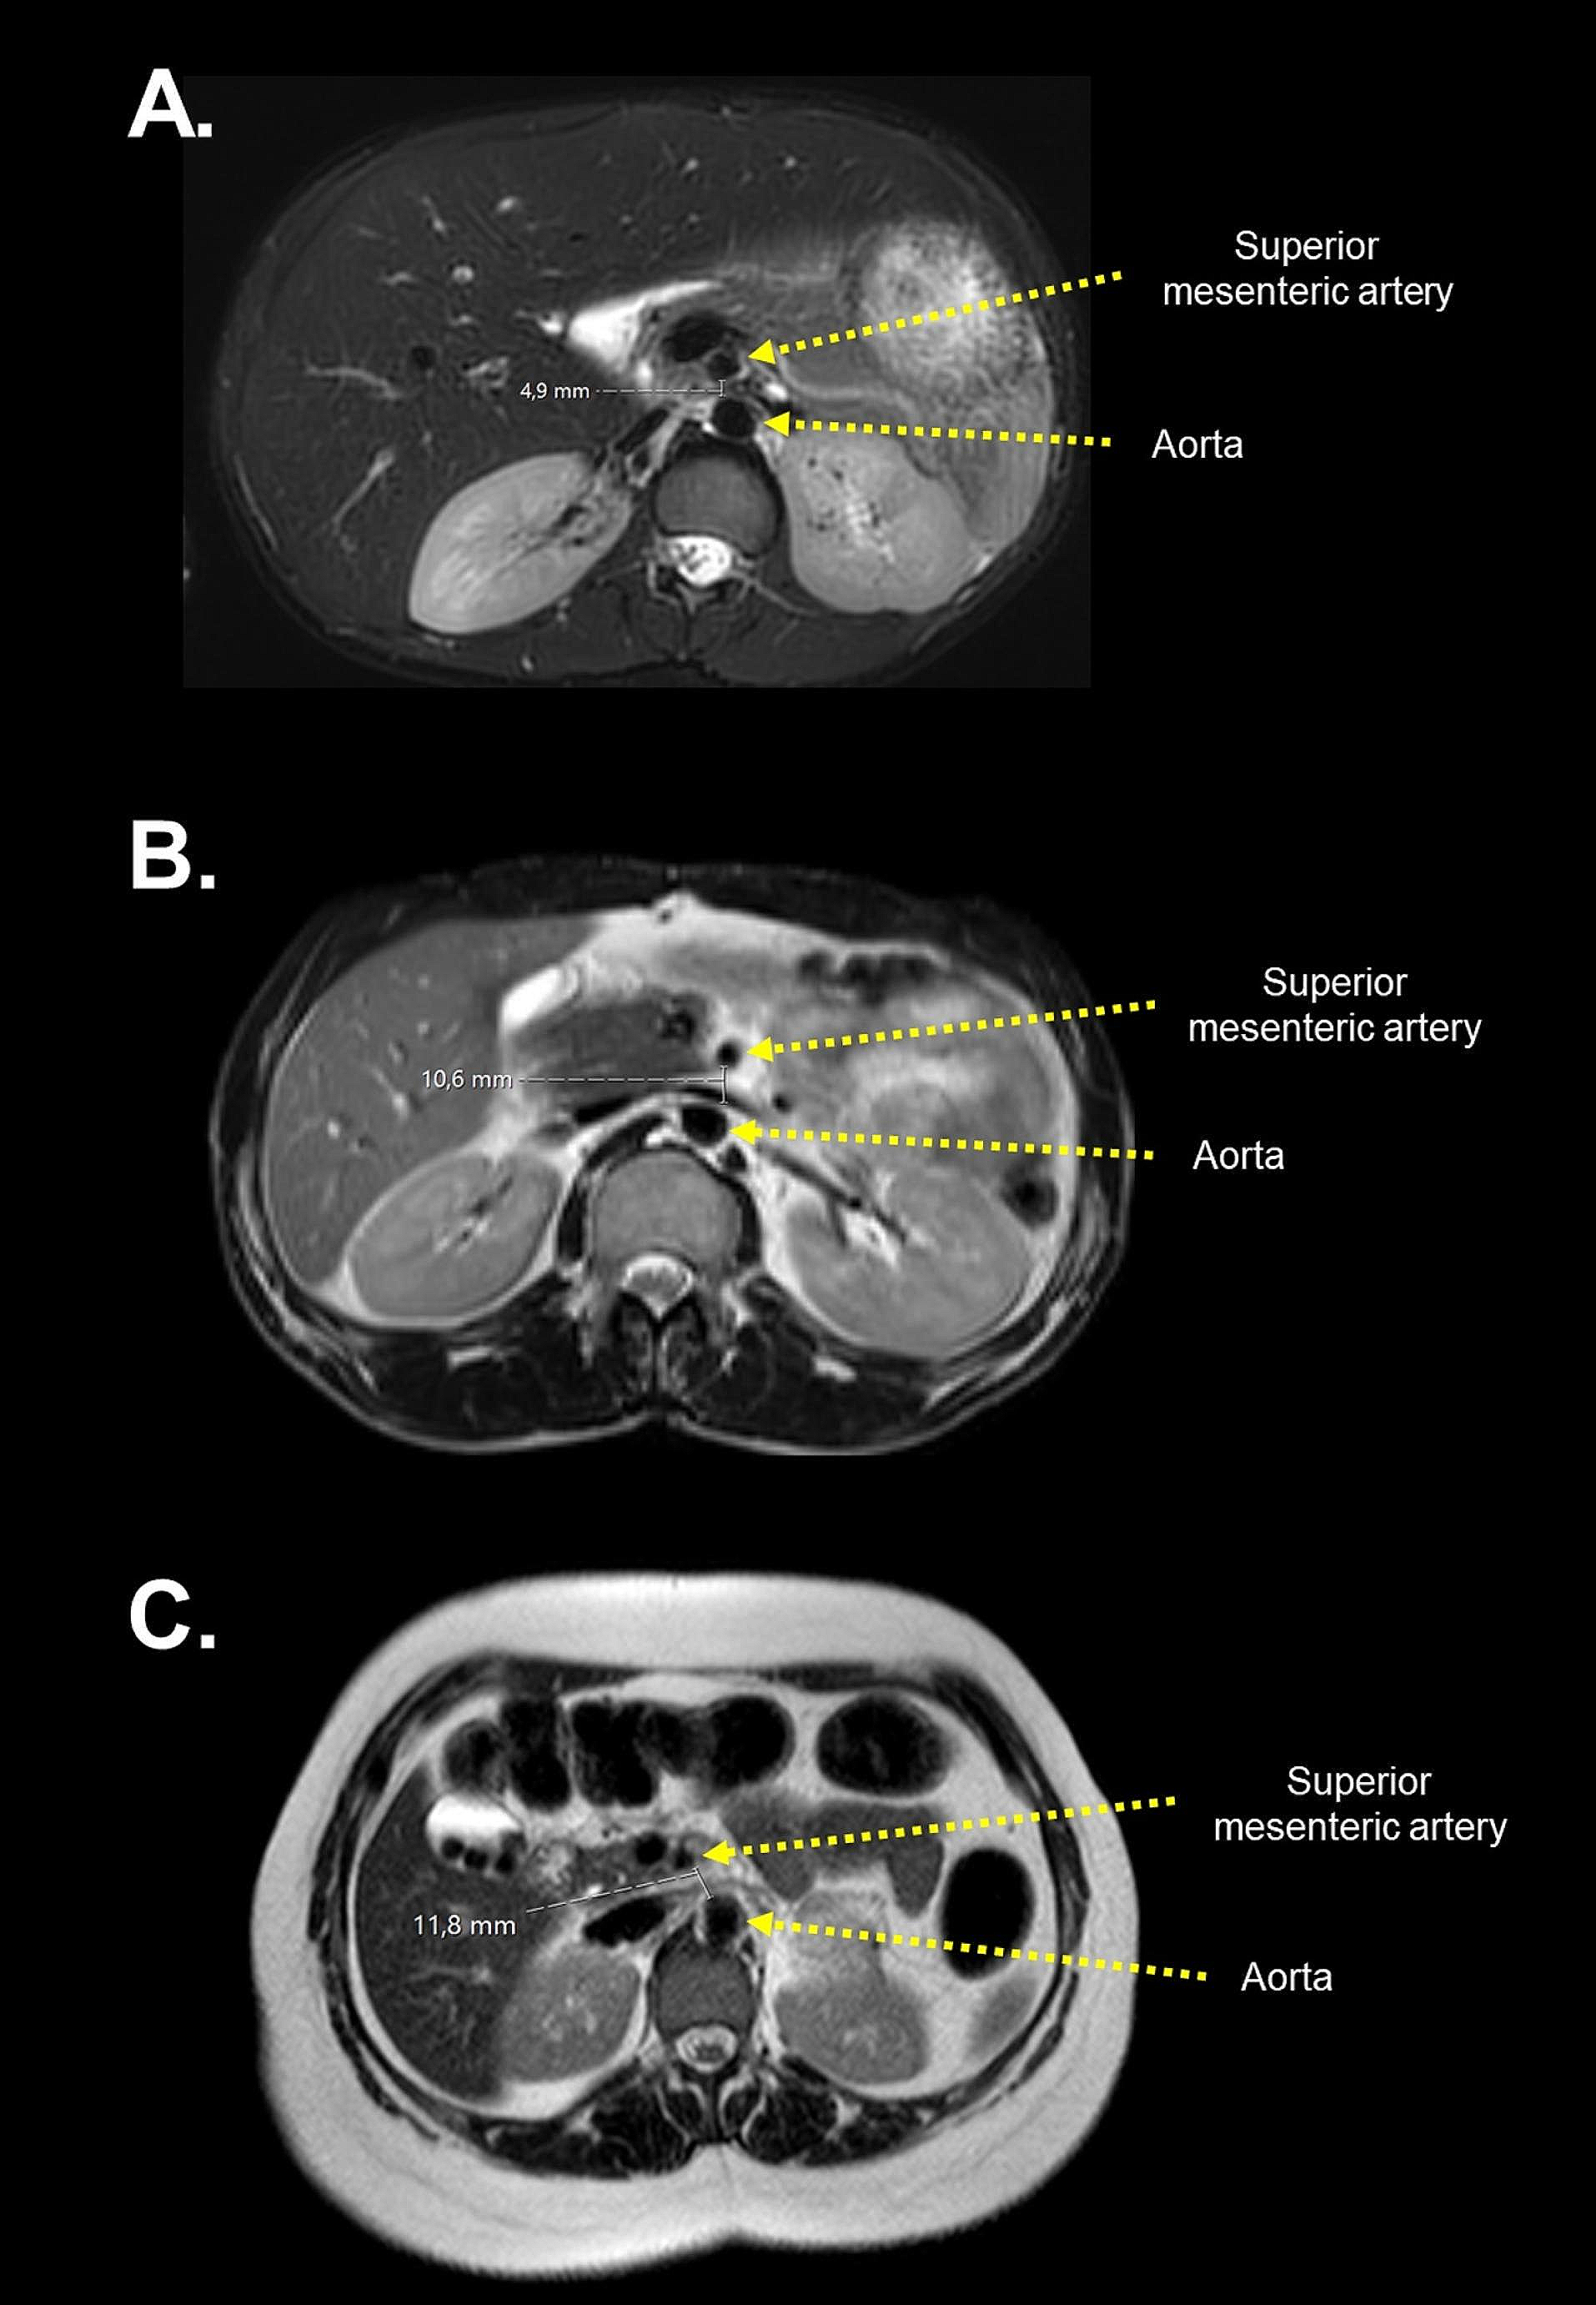

Assessment of aortomesenteric distance and mesenteric and retroperitoneal adipose tissue thickness in genetic forms of lipodystrophy

Lipodystrophy is a rare disease characterized by the loss of adipose tissue. Visceral adipose tissue loss in certain forms...